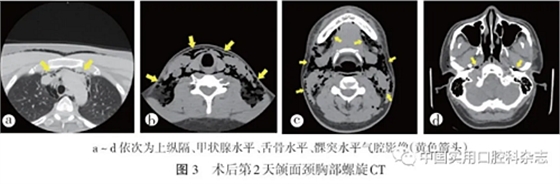

触痛(-);开口度22 mm;38、48拔牙窝周围轻度红肿,无溢脓、无积液,未见缝线。颌面颈胸部螺旋CT示:双侧上纵隔、胸壁、锁骨上区、颈部、口底、颏下区、下颌下区、咽旁间隙、颈深上区、椎前、颈后区、腮腺咬肌区、颊部及左侧颞下窝软组织可见大量气腔影像(图3)

诊断:双侧面颈部皮下气肿;纵隔气肿。